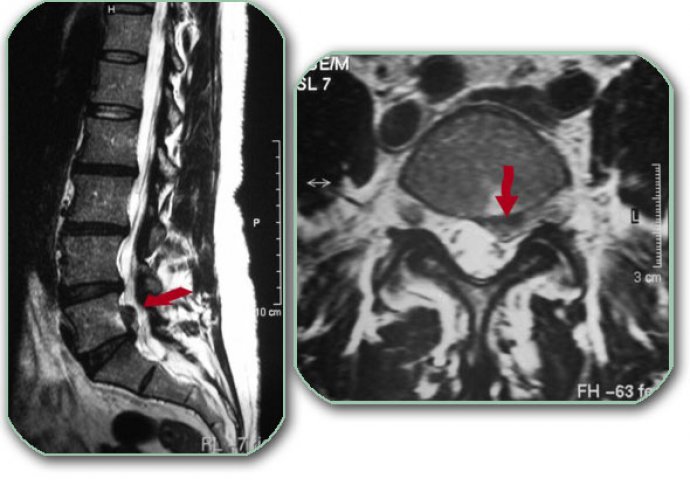

Dakle, ako postoji povreda hrskavice koja se nalazi između kralježaka, tada dolazi do diskopatije.